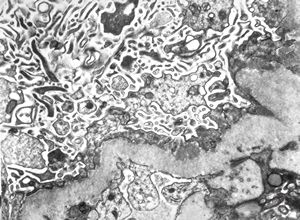

F,14y. | Alport syndrome - split and laminated, thick/thin basement membranes